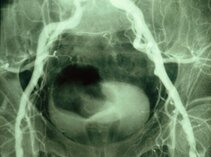

Our research group specializes in molecular and basic science models of clinically relevant topics. Our team is interested, for instance, in developing methods to predict and prevent recurrence of stenotic lesions after catheter interventions.

We have previously evaluated modifications of thrombectomy devices, stents and balloons delivering drugs to the vessel wall, and we have created new methods of ultrasound analysis in vascular medicine.

These images tell a story and we will explain it to you…..